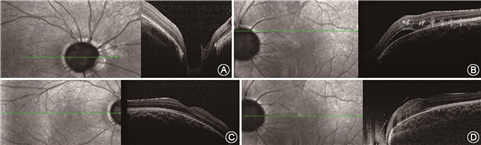

先证者男性,5岁,因自幼双眼内斜视于2019年2月27日就诊于吉林大学第二医院眼科。眼部检查:右眼0.25矫正不提高,左眼0.4矫正至0.5。双眼前节未见明显异常。散瞳检查可见左眼视盘大于右眼,视杯宽而深,有多发睫状视网膜血管自盘周呈放射状发出,类似牵牛花视盘(图1)。左眼可见视盘颞上、颞下方圆形视网膜脱离。相干光层析成像术(optical coherence tomography,OCT)检查结果可见视盘宽而深,左眼可见视网膜神经上皮脱离,双眼黄斑区未见明显异常(图2)。询问其家族史,其父自述自幼右眼视力极差,10年前行肾移植手术,遂对先证者父母及妹妹行眼科检查。

其母未见明显眼部异常,父亲视力为右眼20 cm手动,矫正不提高,左眼0.4矫正至0.8,前节无明显异常,散瞳查眼底可见右眼视盘增大,血管走行异常,盘周可见环形萎缩弧;左眼视盘大小正常,视网膜血管数目增多,自盘周放射状发出,可见视盘鼻侧有髓神经纤维及黄斑区视网膜劈裂(图3)。OCT同样可见视杯深而宽,左眼黄斑区及盘周视网膜劈裂,右眼黄斑区视网膜神经上皮浅脱离(图4)。先证者妹妹双眼矫正视力为0.2,眼前节未见明显异常,散瞳查眼底可见双眼视盘大小、血管数量及走行大致正常,视杯宽而深,颞侧盘沿窄(图5)。OCT可见宽而深的视杯,黄斑区未见明显异常(图6)。